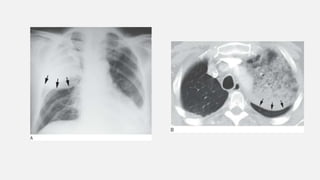

• #21 Right lung consolidation due to pulmonary edema. Air bronchograms are visible bilaterally within the consolidated lung, and pulmonary vessels are obscured.

• #22 Enhanced CT in a patient with right middle and lower lobe pneumonia shows homogeneous consolidation, preserved lung volume, air bronchograms (black arrows), and opacified vessels (white arrows), appearing denser than surrounding consolidated lung (i.e., the “CT angiogram” sign).Preserved Lung Volume In the presence of consolidation, because alveolar air is replaced by something else the volume of affected lung tends to be preserved

• #24 Consolidation: patchy opacities. A: Chest radiograph in a patient with pulmonary edema due to renal failure shows patchy perihilar consolidation. B: Patchy areas of fluffy consolidation are seen on CT. The fluffy margins are due to variable involvement of alveoli at the edges of the pathologic process.